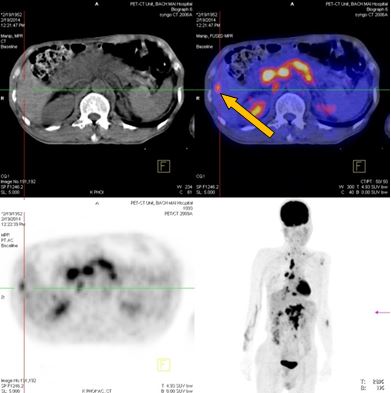

-          Bệnh nhân đã được tiến hành chụp PET/ CT đánh giá, kết quả:

+ Vùng phế quản gốc phải có khối KT 2,4x1,7cm, tăng hấp thu F-18 FDG, max SUV=8,50. Hạch trung thất kích thước lớn nhất 3,1x3,5cm, max SUV=10,29

+ Hạch thượng đòn phải KT 1,1cm, tăng hấp thu F-18 FDG, max SUV=5,67; Hạch thượng đòn trái KT 0,8cm, max SUV=3,97. Tổn thương cung sau xương sườn số 2 bên phải tăng hấp thu F-18 FDG, max SUV=3,13.

+ Nhiều hạch ổ bụng dọc theo ĐM chủ bụng tạo thành khối lớn KT 8,5x5,1 cm và 5,1x3,9cm, tăng hấp thu F-18 FDG, max SUV=10,45. Nhu mô gan hạ phân thùy VI có nốt KT 1,2cm, tăng hấp thu F-18 FDG, max SUV=4,15.

- Trước điều trị: Khối u 2,4x1,7cm, max SUV=8,50. Hạch dưới carina KT 3,1x3,5cm, max SUV=10,29

- Sau điều trị 4 thángKhông rõ u, không có hạch trung thất

-Trước điều trị: Nhiều hạch ổ bụng dọc theo ĐM chủ bụng tạo thành khối lớn KT 8,5x5,1 cm và 5,1x3,9cm,  max SUV=10,45.

-Sau điều trị 4 tháng: Không có hạch ổ bụng